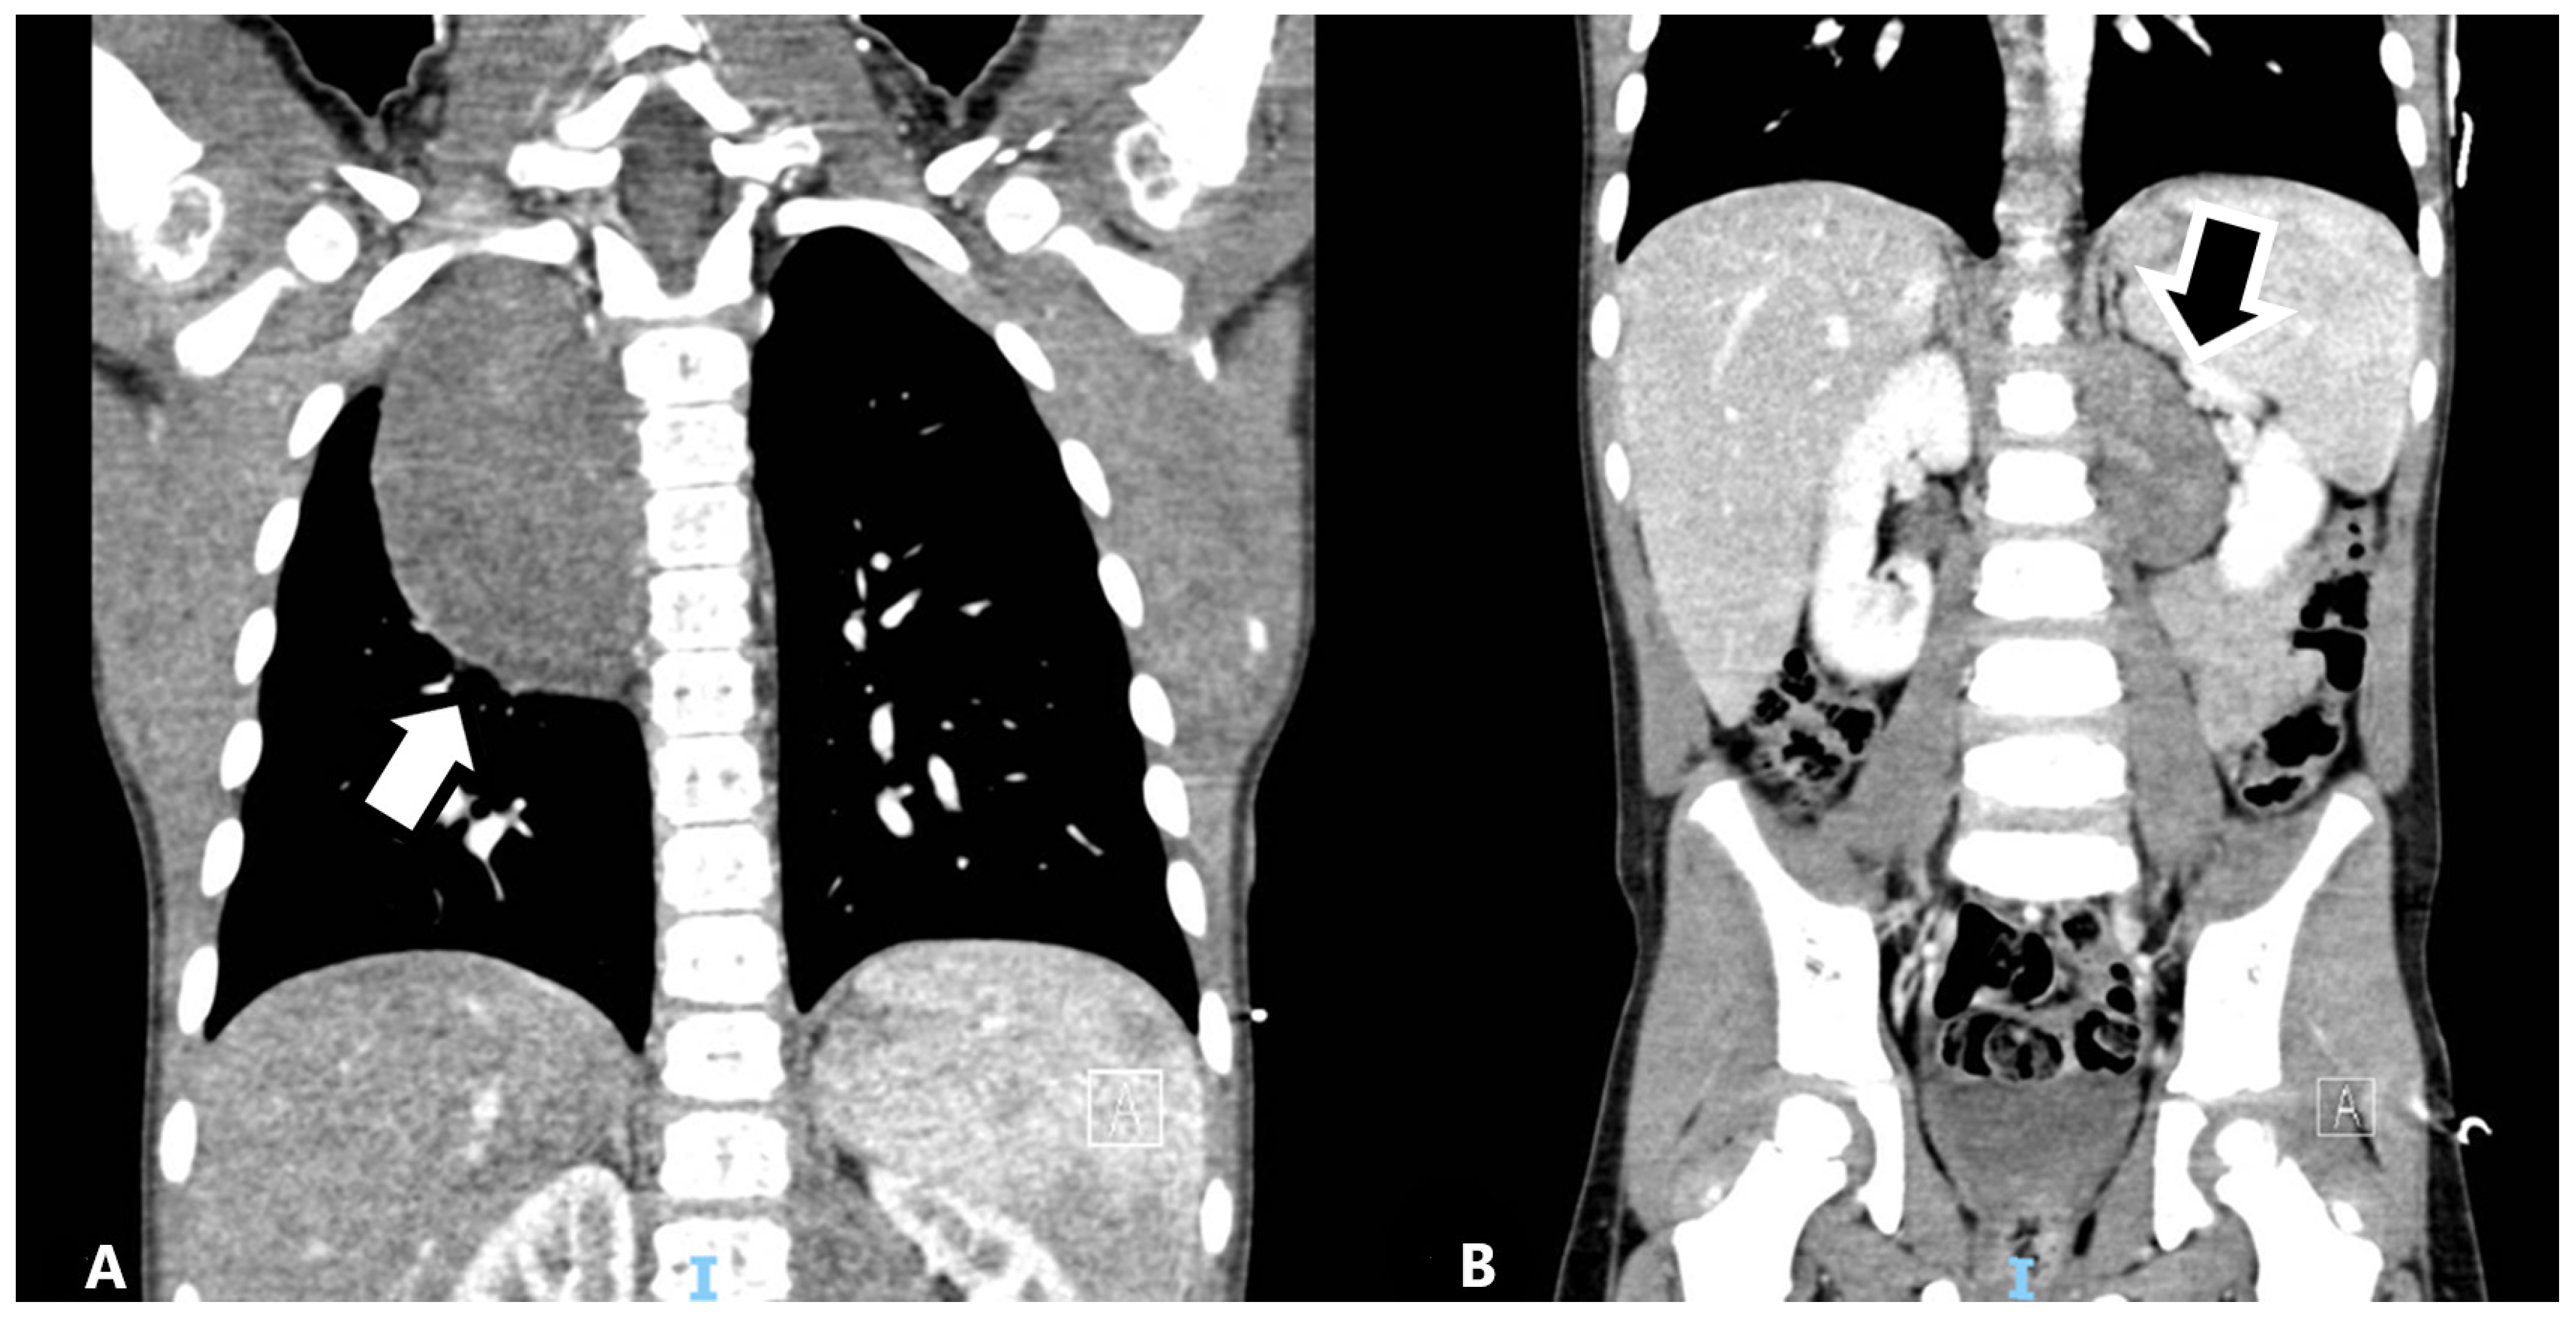

Figure 7. Reevaluation with MRI showed the thoracic lesion with unchanged features (A), and a residual tumor >2 cm at abdominal lesion (B) with a local enlarged lymph node (C). Clinical (L2 stage and age >18 months), histological and molecular features (MYCN not amplified and presence of SCAs) led to classification into the intermediate risk group according to the Low/Intermediate risk Neuroblastoma European Study (LINES) [2].